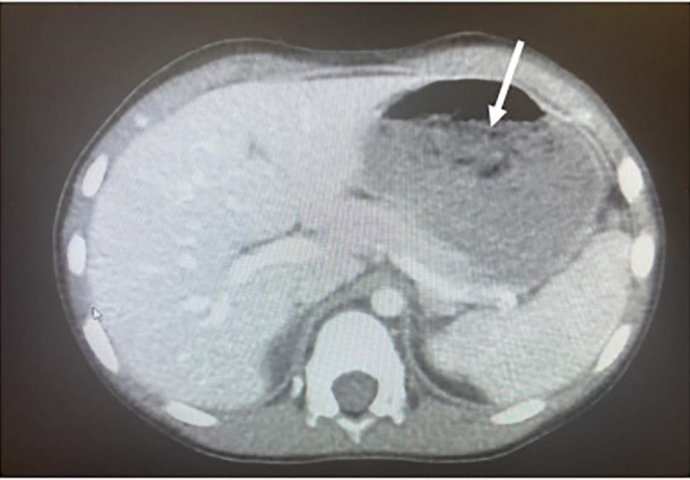

Prema njihovom izvještaju, dječak je hitno prevezen u bolnicu. Medicinski tim iz Klivlendske klinike uradio je odmah skeniranje njegovog stomaka i karlice. I imali su šta i da vide. Snimak je pokazao da su komadići žvake blokirali 25% njegovog stomaka i gastrointestinalnog trakta. Ljekari su dječaku morali metalnom cijevkom kroz grlo da uklone žvake iz stomaka. Ovo je svakako rijedak slučaj, ali nauk za sve ostale.